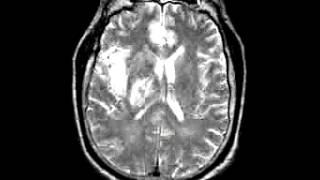

Cerebrovascular Disease Multiple embolic infarction, diffusion and FLAIR imaging